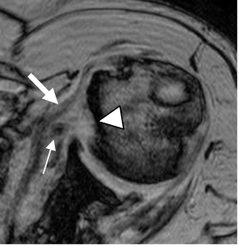

Fig 91. Pinzamiento interno anterior.

RM axial en FFE. Osteofito en la glenoides anterior, que erosiona la cabeza humeral. (Cabeza de Flecha). Hay luxación de la porción larga del bíceps (Flecha delgada), permaneciendo integro el tendón del subescapular. (Flecha gruesa).